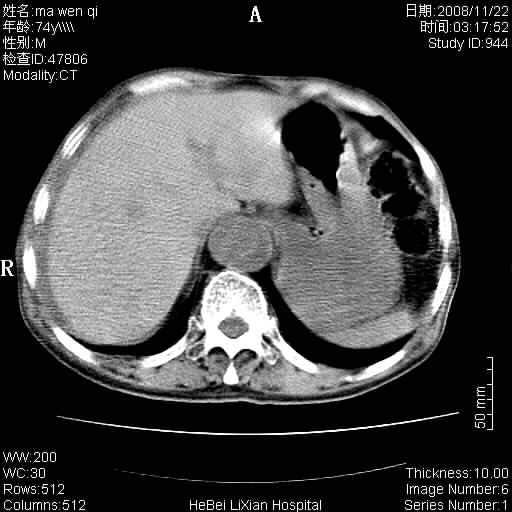

患者男 74岁.突然昏迷,休克6小时.血压70/30,头颅ct未见异常,既往体健.

补充病史,保留导尿10小时,尿袋内只有少许尿液,患者于住院后15小时后去世.

腹主动脉、双侧髂动脉夹层动脉瘤破裂出血进入腹腔。

1)考虑双侧髂动脉瘤并右侧动脉瘤破裂出血,右侧腹膜后及腹腔积血。2)双侧腹股沟疝。

1)考虑,腹主动脉、双侧髂动脉夹层动脉瘤破裂伴右侧腹膜后及腹腔积血。2)双侧腹股沟疝。

1)考虑胸、腹主动脉、双侧髂动脉瘤并右侧动脉瘤破裂出血,右侧腹膜后及腹腔积血。2)双侧腹股沟疝。